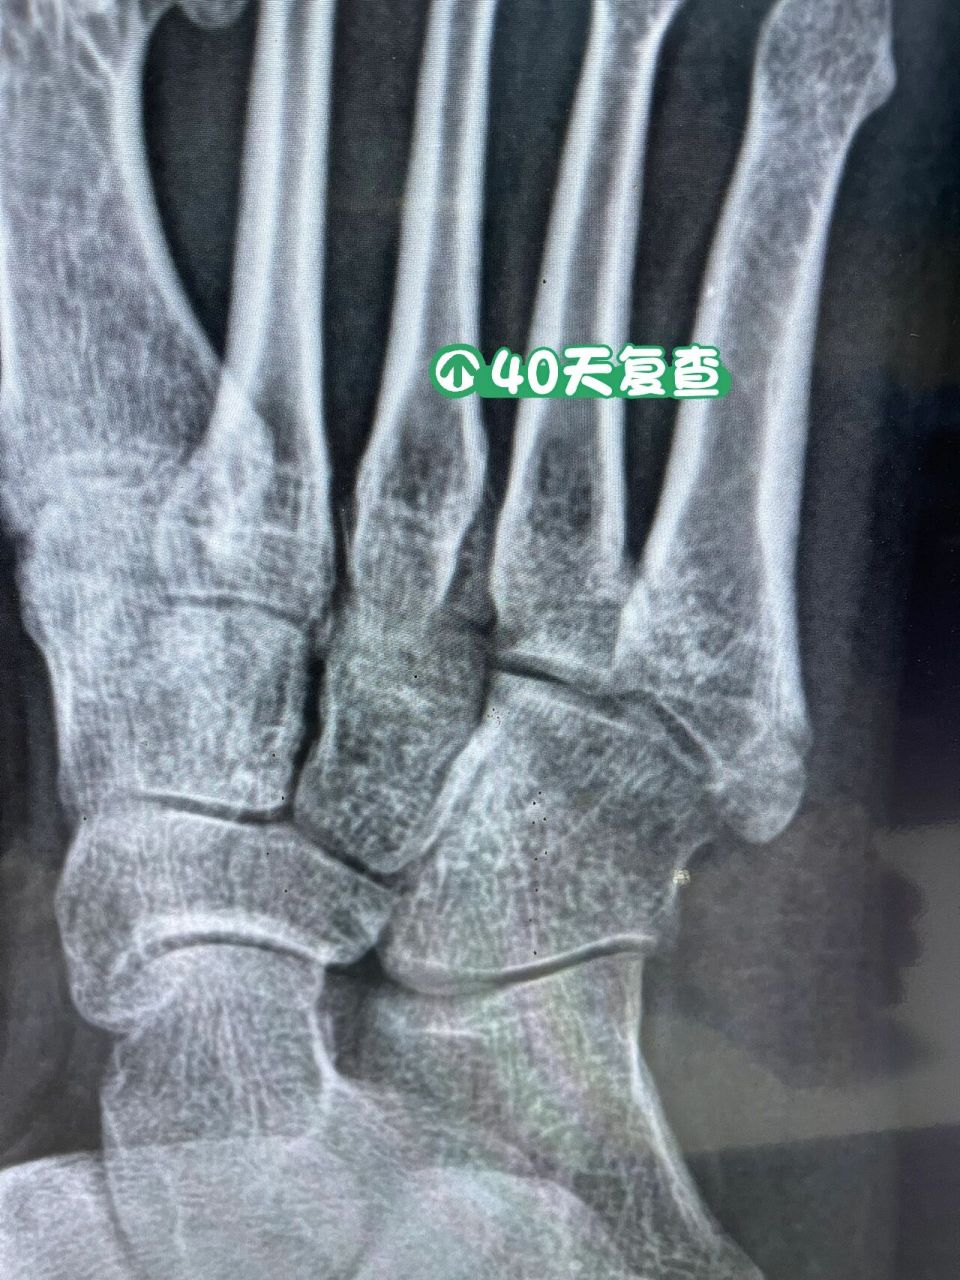

第五跖骨基底骨折40天复查 骨折40天了,还有一点缝,脱拐走路一星期